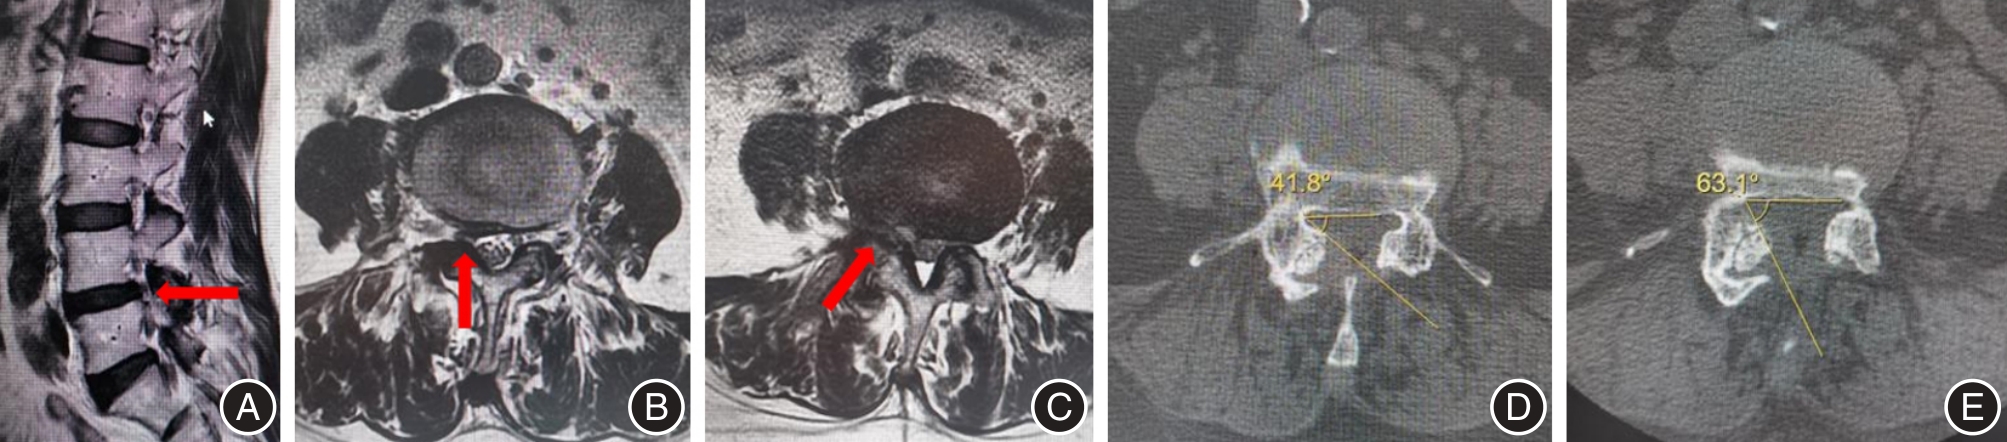

| LRA | 术前 | 32.50 ± 9.30 | 34.23 ± 7.86 | -1.73(-6.63 ~ 3.17) | -0.710 | 0.481 |

| 术后3 d | 69.86 ± 5.22* | 72.84 ± 6.07* | -2.98(-6.20 ~ 0.24) | -1.861 | 0.069 |